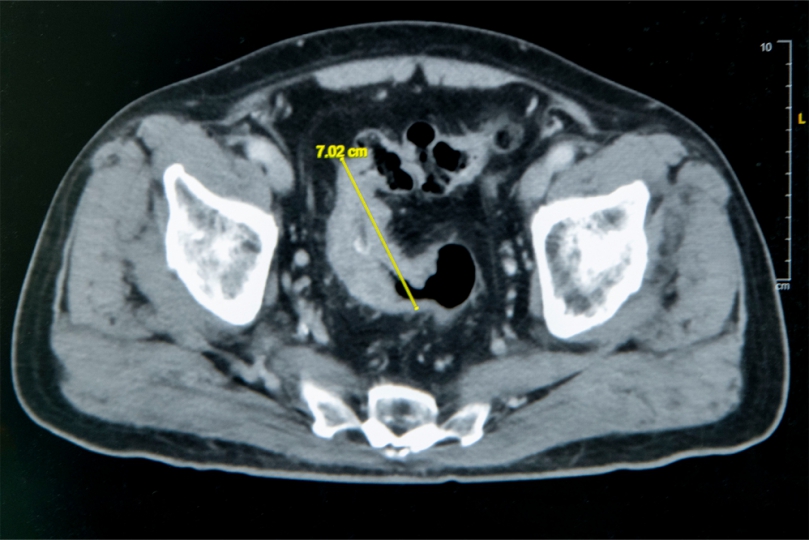

張譽耀主任說,老翁罹患「乙狀結腸癌」,腫瘤7公分,造成腸子幾乎完全阻塞,也導致老翁一進食肚子就脹又痛,術前因不敢進食,老翁體重下降,營養不足,造成傷口癒合不良,老翁手術有兩個傷口,一個在肚子上,一個在腸子,腸子傷口癒合不良,會造成腸吻合滲漏,到時就須做人工肛門,幸好提早住院,透過靜脈營養針先建立營養,讓病人強健身體,再手術,術後傷口順利癒合。